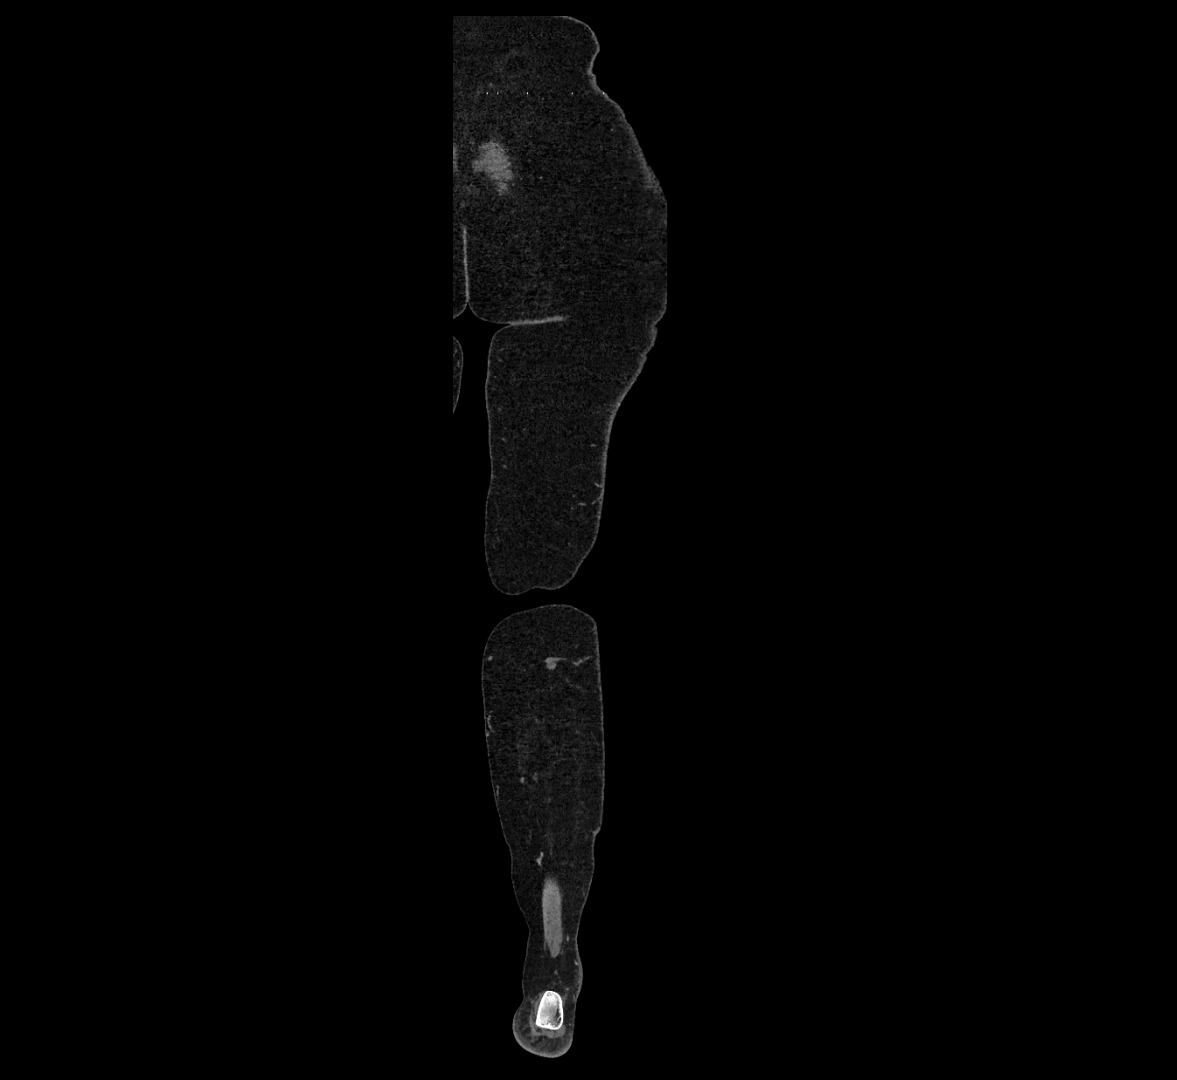

CT images

image